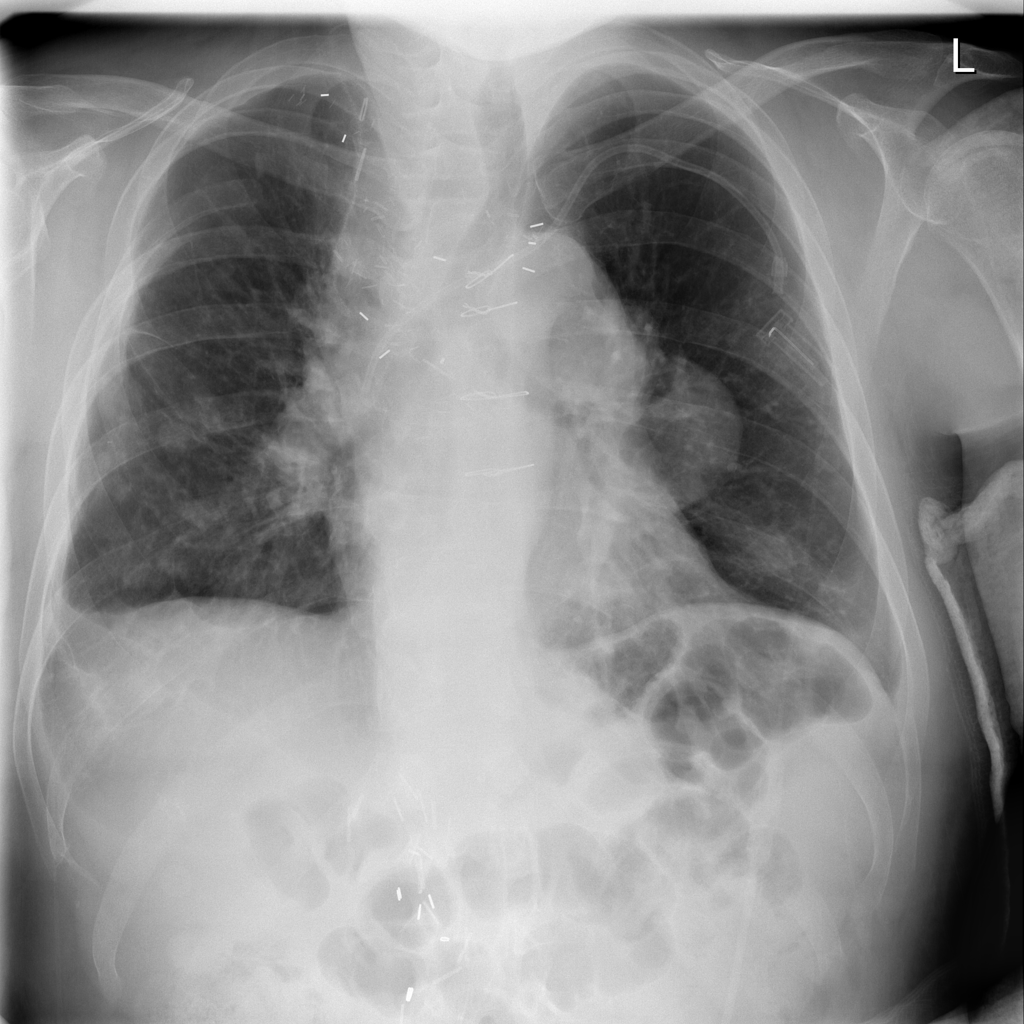

Mass

A mass is a larger focal opacity or lesion seen on the image. It is a descriptive finding that can have several causes and usually needs more imaging or clinical context to characterize.

PAT-D7A5 · IMG-000Mass

PAT-D7A5 · IMG-000

PA